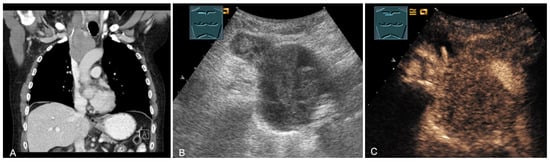

The spectrum of primary mediastinal masses includes a heterogeneous group of benign and malignant pathologies [28,31,36]. Benign primary mediastinal masses include congenital cysts (Figure 14), lipomas, thyroid tissue (Figure 15), benign thymomas, thymic residues, scar tissue, ganglioneuromas (Figure 16), schwannomas (Figure 17), and giant cell tumors (Figure 18) [28,31,36].

Figure 16.

A young patient with tumor formation in the paravertebral mediastinum on CT (provided by Prof. Dr. Andreas H. Mahnken, Marburg, Germany) (A), B-mode US (B), and CEUS (C), surgically confirmed as ganglioneuroma.